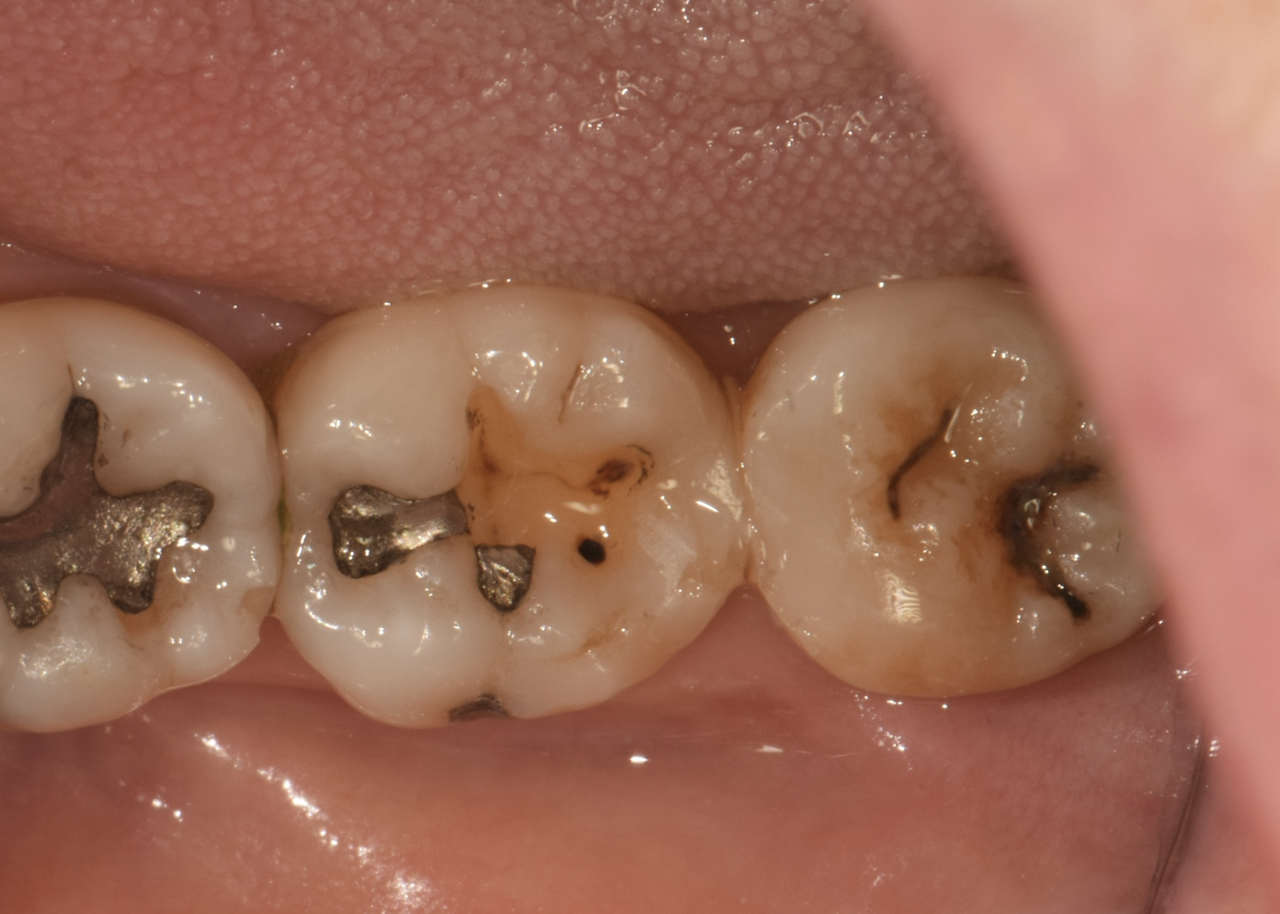

진단 및 검사

사랑니의 위치와 상태를 평가하기 위해 X-레이 촬영과 구강내 검진을 진행합니다.